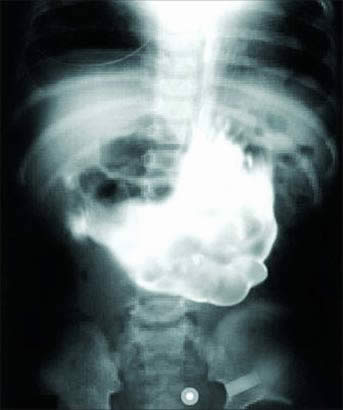

2. Gumpalan rambut

Perempuan 18 tahun asal Kirgistan, Ayperi Alekseeva mengaku merasakan sakit di bagian perut setiap kali makan dan minum.

Ketika diberikan tindakan medis berupa operasi di Rumah Sakit Bishkek, diketahui bahwa sakitnya itu disebabkan oleh gumpalan rambut yang bersarang di perutnya. Ini dikarenakan Alekseeva mengidap Trichophagia yaitu kesukaan mengunyah rambut dan tali-talian.